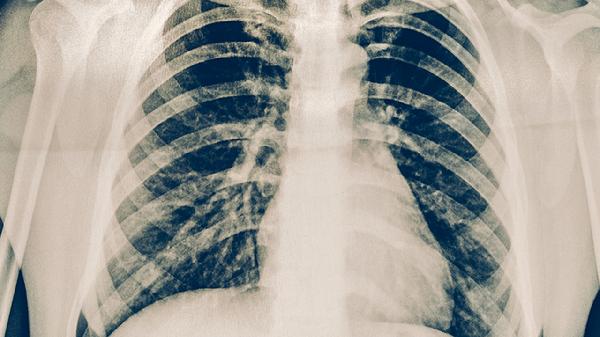

肺結(jié)核是由結(jié)核分枝桿菌引起的慢性傳染病,主要危害包括肺部組織損傷、傳染風(fēng)險(xiǎn)、全身多系統(tǒng)并發(fā)癥等。肺結(jié)核的危害主要有肺部空洞形成、呼吸功能衰竭、結(jié)核性腦膜炎、播散性結(jié)核病、藥物性肝損傷等。

結(jié)核分枝桿菌破壞肺組織后可能形成薄壁空洞,導(dǎo)致持續(xù)性咳嗽、咯血等癥狀??斩磧?nèi)壞死物質(zhì)可能成為細(xì)菌繁殖的溫床,增加治療難度。長(zhǎng)期未控制的空洞病變可能誘發(fā)支氣管擴(kuò)張或肺纖維化。

廣泛肺實(shí)質(zhì)破壞會(huì)顯著降低肺換氣功能,出現(xiàn)活動(dòng)后氣促、低氧血癥等表現(xiàn)。重癥患者可能出現(xiàn)二型呼吸衰竭,需長(zhǎng)期氧療支持。部分患者即使治愈后仍遺留限制性通氣功能障礙。